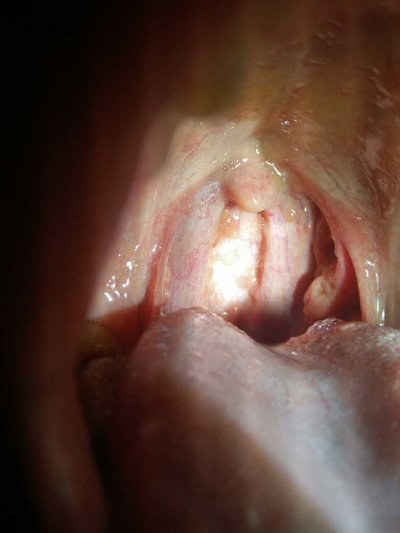

Lichen planus is a common chronic inflammatory disease. The symptoms of oral lichen planus are easily confused with oral ulcer at the beginning. There were no special symptoms at first. And some patients in eating spicy stimulating things when local burning pain feeling. Some patients will feel rough mucosa, there is a sense of wood astringency, inducing oral lichen planus factors also have many. For example, long-term external use or internal use of certain drugs, or some patients with low immunity. Let's take a look at the symptoms of oral lichen planus.

At the beginning, lichen planus has no special symptoms. The upper lip is more than the lower lip. It's easy to crack and reappear after blistering. The other is erosive type, which is quite similar to oral ulcer. Although this disease will not affect the work, it can not be ignored.

Oral lichen planus is generally symmetrical. But it is also possible to have lesions, so for patients with this kind of disease to be treated in time, there are many kinds of treatment methods, there are oral drugs or some topical drugs, but can not use drugs indiscriminately, to go to the hospital after examination.